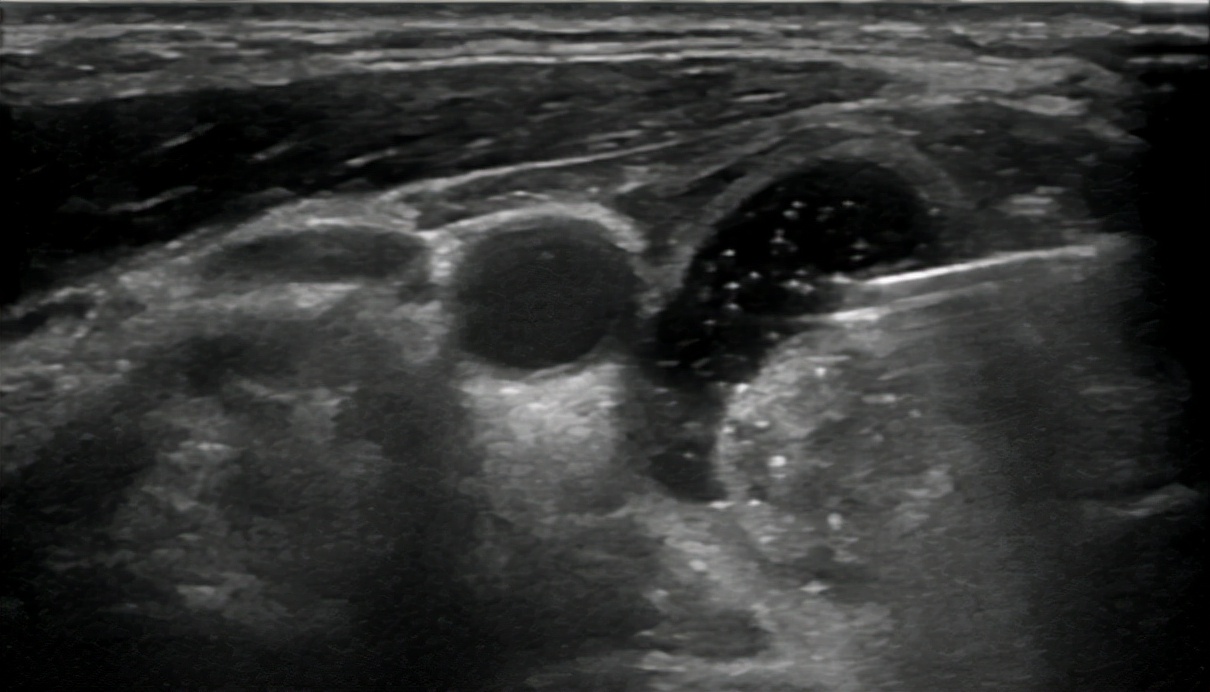

介入超声主任医师石洪柱先给张女士进行了甲状腺结节超声造影,进一步明确了结节边界、内部结构、血供情况以及与周围重要血管神经关系。

对结节囊性部分穿刺抽液+硬化治疗。抽出褐色粘稠囊液,生理盐水冲洗囊腔,聚桂醇硬化囊壁。

治疗前结节图像

囊腔穿刺

抽吸囊液、冲洗囊腔